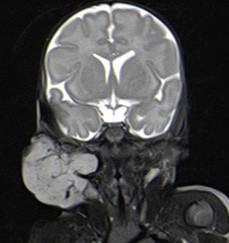

Na RM, identificou-se assimetria do volume das parótidas, por marcado aumento da direita, devido a lesão interessando os seus lobos superficial e profundo, de contornos regulares e limites bem definidos, com maior eixo de 48 mm (Figs. 3 e 4). A extensão da lesão ao lobo profundo da glândula parótida direita determinava desvio medial da gordura parafaríngea, sem repercussão sobre o contorno da coluna aérea faríngea. Apesar das características semiológicas por imagem da lesão parotídea direita não serem específicas, atendendo às características clínicas da alteração cutânea apresentada pela examinada na mesma região, considerou-se a hipótese diagnóstica mais provável de hemangioma infantil misto. Na apreciação sumária do parênquima encefálico conseguida não se identificaram aspetos malformativos, em particular da fossa posterior, nem aspetos suspeitos de hemangiomas intracranianos.

Figura 3: RM, corte coronal com ponderação em T2 FS: marcado aumento da parótida direita, devido a lesão interessando os seus lobos superficial e profundo, bem delimitada e de contornos regulares.